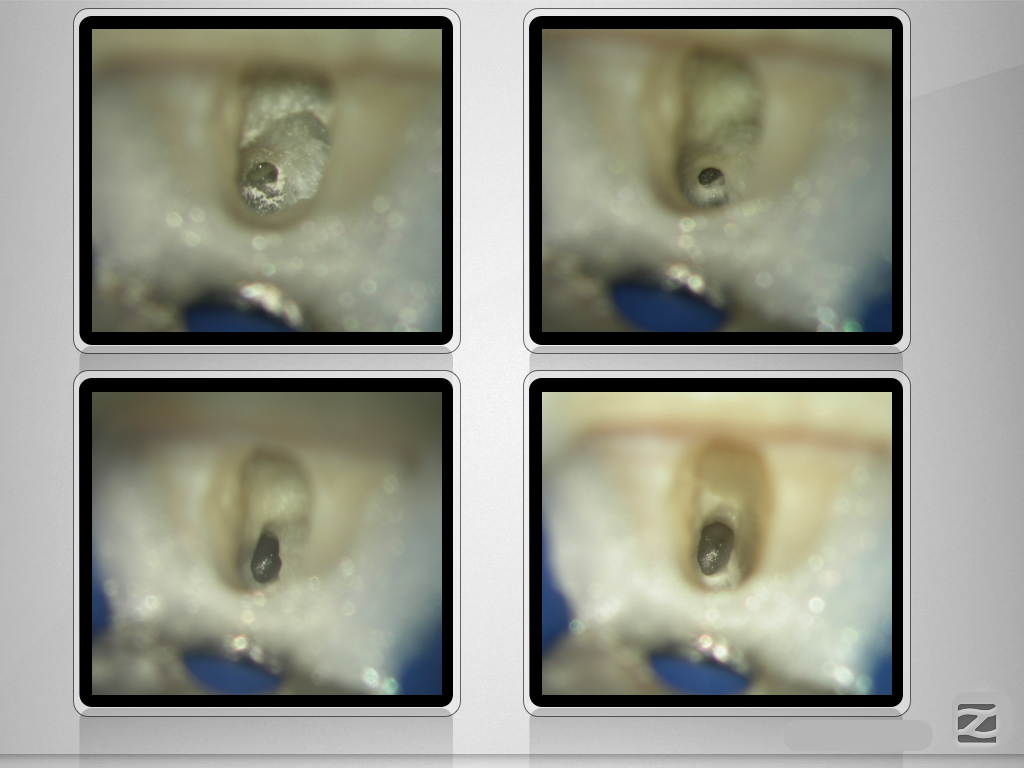

Folgen eines Milchzahntraumas (3)